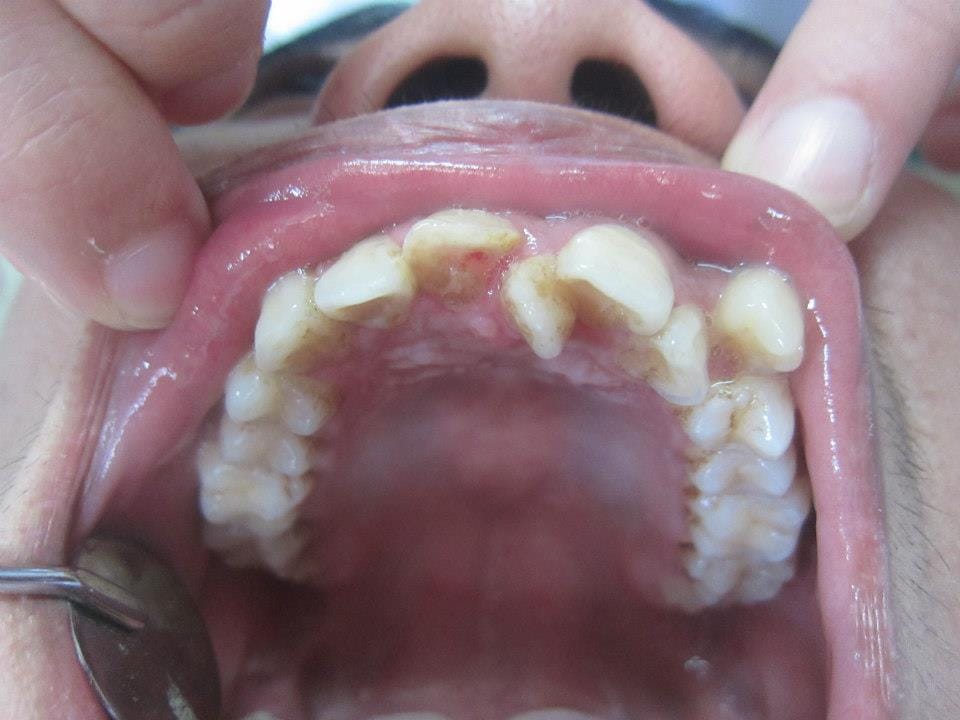

răng thừa mọc giữa 2 răng cửa

Răng thừa mọc giữa 2 răng cửa có thể thẩm mỹ bằng bọc răng sứ hay niềng răng cố định

Những trường hợp có răng thừa mọc giữa hai răng cửa như của em, chúng tôi gọi là răng dư. Phác đồ điều trị trong những trường hợp như của em thường mất khá nhiều thời gian và tương đối phức tạp.

Răng dư là răng mọc thêm, ngoài những răng bình thường  và có thể được tìm thấy hầu như ở bất kỳ vị trí nào trên khung hàm. Tuy nhiên, hầu hết các răng dư đều được phát hiện ở răng cửa trước, hàm trên. Như trường hợp của em.

Răng dư hay răng thừa mọc giữa 2 răng cửa không gây bất kỳ biến chứng hay tiềm ẩn nguy cơ nào đối với sức khỏe răng miệng. Tuy nhiên, nó lại ảnh hưởng rất nhiều đến vẻ thẩm mỹ của hàm răng.